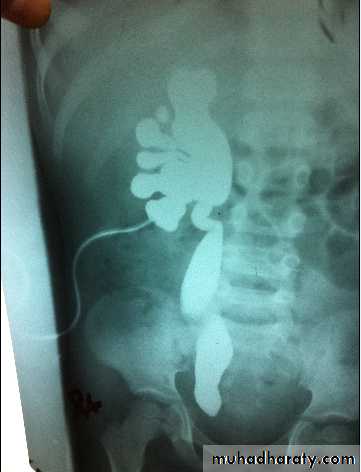

What's the imaging study &DiagnosisVUR grade 5 voiding cystourethrogram